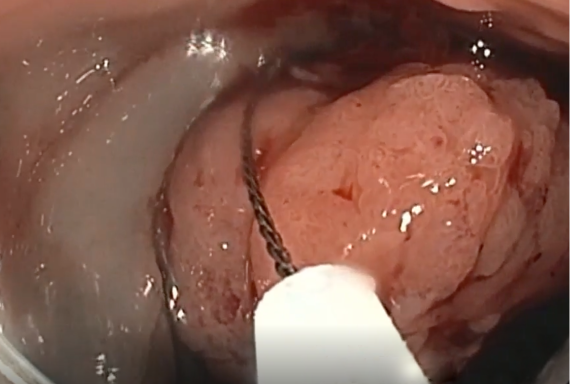

Basic EMR, Hybrid ESD and ESD

Case studies from the leading edge of EMR and ESD

Hear first-hand from physicians at the forefront. Learn what’s possible now and stay informed about what’s next.